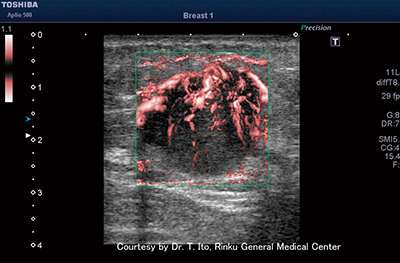

図2 リンパ節のcSMI画像

リンパ節内の微小な血流がSMIによってとらえられている。